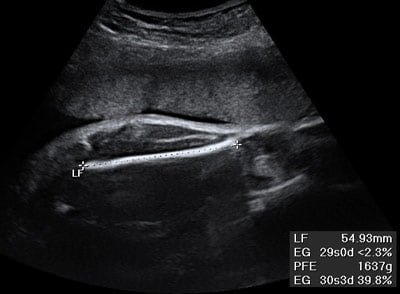

Ecografía de un bebé en crecimiento

Según fuentes cercanas a la pareja, el embarazo de Evaluna está avanzando de forma favorable y se espera que el segundo bebé de Camilo y Evaluna nazca en los próximos meses. Aunque se ha mantenido cierto hermetismo en torno a la noticia, algunos detalles han trascendido a los medios de comunicación.

Se ha filtrado que Evaluna ha seguido un estricto control médico durante este embarazo, realizándose todas las pruebas necesarias para garantizar el bienestar tanto de ella como del bebé. Este enfoque en la salud materno-fetal es fundamental para asegurar un desarrollo óptimo del segundo bebé de la pareja.

Es importante destacar la importancia de llevar un estilo de vida saludable durante el embarazo, incluyendo una dieta balanceada, ejercicio moderado y el seguimiento de las indicaciones médicas. Estos cuidados contribuyen significativamente al bienestar de la madre y al adecuado crecimiento del bebé.